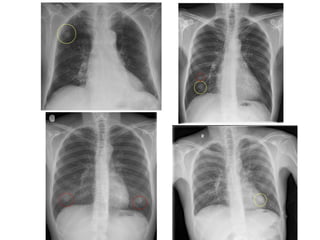

nodular

Se produce cuando se

acumulan lesiones más o

menos esféricas dentro del

intersticio.

El nódulo intersticial difiere

del nódulo de espacio aéreo

en que es homogéneo, bien

circunscrito y definido,

uniforme.

Micronodular (1 mm)

pequeño (1-3 mm)

Mediano (3-5 mm)

Nunca confluyen para formar

condensaciones.